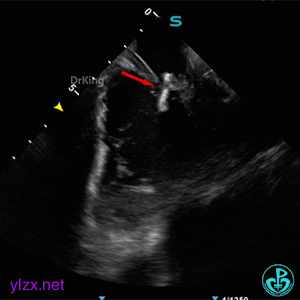

封堵器完全释放后位置、形态观察

封堵器完全释放后盘面平整,呈“工”字型骑跨于室间隔两侧,未见瓣膜影响。